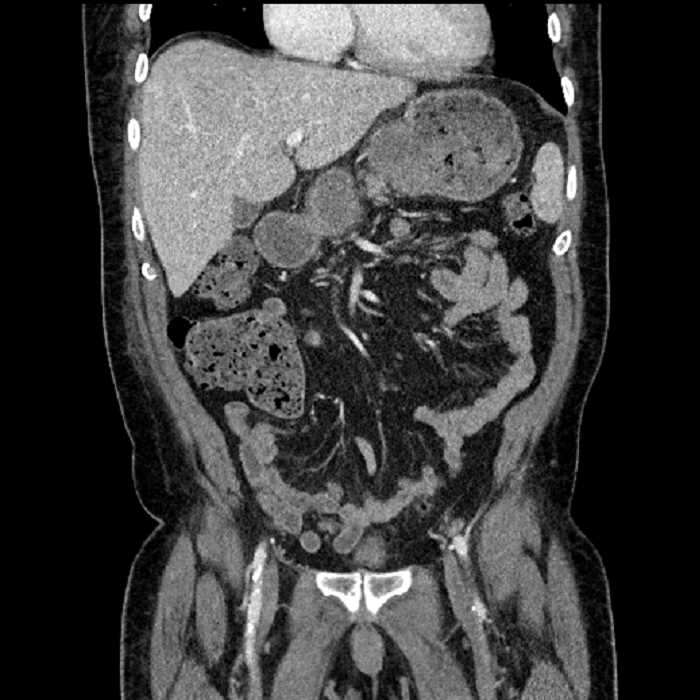

• Large fluid density structure in hepatic segments 7 and 8 measuring 10 x 7 x 7 cm with internal septation and circumferential ill-defined low density compatible with edema

• Peripherally enhancing subcapsular collections along the anterior margin of the left hepatic lobe measuring 3 x 1 cm and 2 x 1 cm

• Clearly marginated fluid density structure in segment 7 and several other scattered tiny hypodensities, which likely represent cysts

• Hepatic abscess

Acute sigmoid diverticulitis complicated by a small contained perforation and a large abscess in the right hepatic lobe. Additional small subcapsular abscesses along the anterior margin of the left hepatic lobe.

Additionally, loss of the normal fat plane between the peridiverticular collection and adjacent thickened loops of small bowel raises the potential for an enterocolonic fistula.

• The classic CT imaging appearance is a double target sign with internal low density surrounded by an internal enhancing rim (capsule) and a low density external rim (edema)

• Abscesses may be unilocular or multilocular

• Gas is present in a minority of cases

• Unfortunately, necrotic tumors can have an overlapping imaging appearance, so it is important to follow these to resolution

Hepatic abscess showing the double target sign with low density internally surrounded by a thin inner enhancing rim (red arrow) and ill-defined outer low density rim (yellow arrow). Blue arrow indicates an internal septation. Red arrows: additional smaller subcapsular abscesses. Red arrow: focal contained perforation associated with diverticulitis.